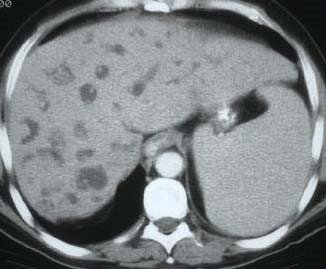

• Əksər hallarda (70%) çoxsaylı olur və qaraciyərin hər iki payını tutarlar.

• Ölçüləri bir neçə millimetrdən bir neçə santimetrə qədər dəyişə bilər.

• Tək şişlər adətən sağ payı tutar.

• Əksəriyyəti arerial qanla qidalanırlar, sürətli qan axınına malikdirlər, lakin hipovaskulyardırlar.

• Törəmə ətrafında kapsula olmur, lakin reaktiv bölgə ola bilir ki, bu da USM-də hipoexoik haşiyə kimi görünə bilir.

• Kolorektal metastazların spesifik diaqnostik əlaməti yoxdur, diaqnoz kriteriyalara və differensiasiyaya əsasən qoyulur.

• Görüntüləmə üsulları diaqnozun dəqiqləşdirilməsində və mərhələnin təyinində önəmlidir.

• CEA artması diaqnozu dəstəkləyir, artmaması isə inkar etmir.

• Biopsiya differensial diaqnostika çətinliyi olarsa tətbiq edilir.

Diaqnostik kriteriyaları:

• Hazırda və anamnezdə kolorektal xərçəng.

• Görüntüləmədə bədxassəli şişlərə məxsus kontrastlaşma (arterial fazada periferik kontrastlaşma, venoz fazada yuyulma).

• Biopsiyada adenokarsinoma metastazı.